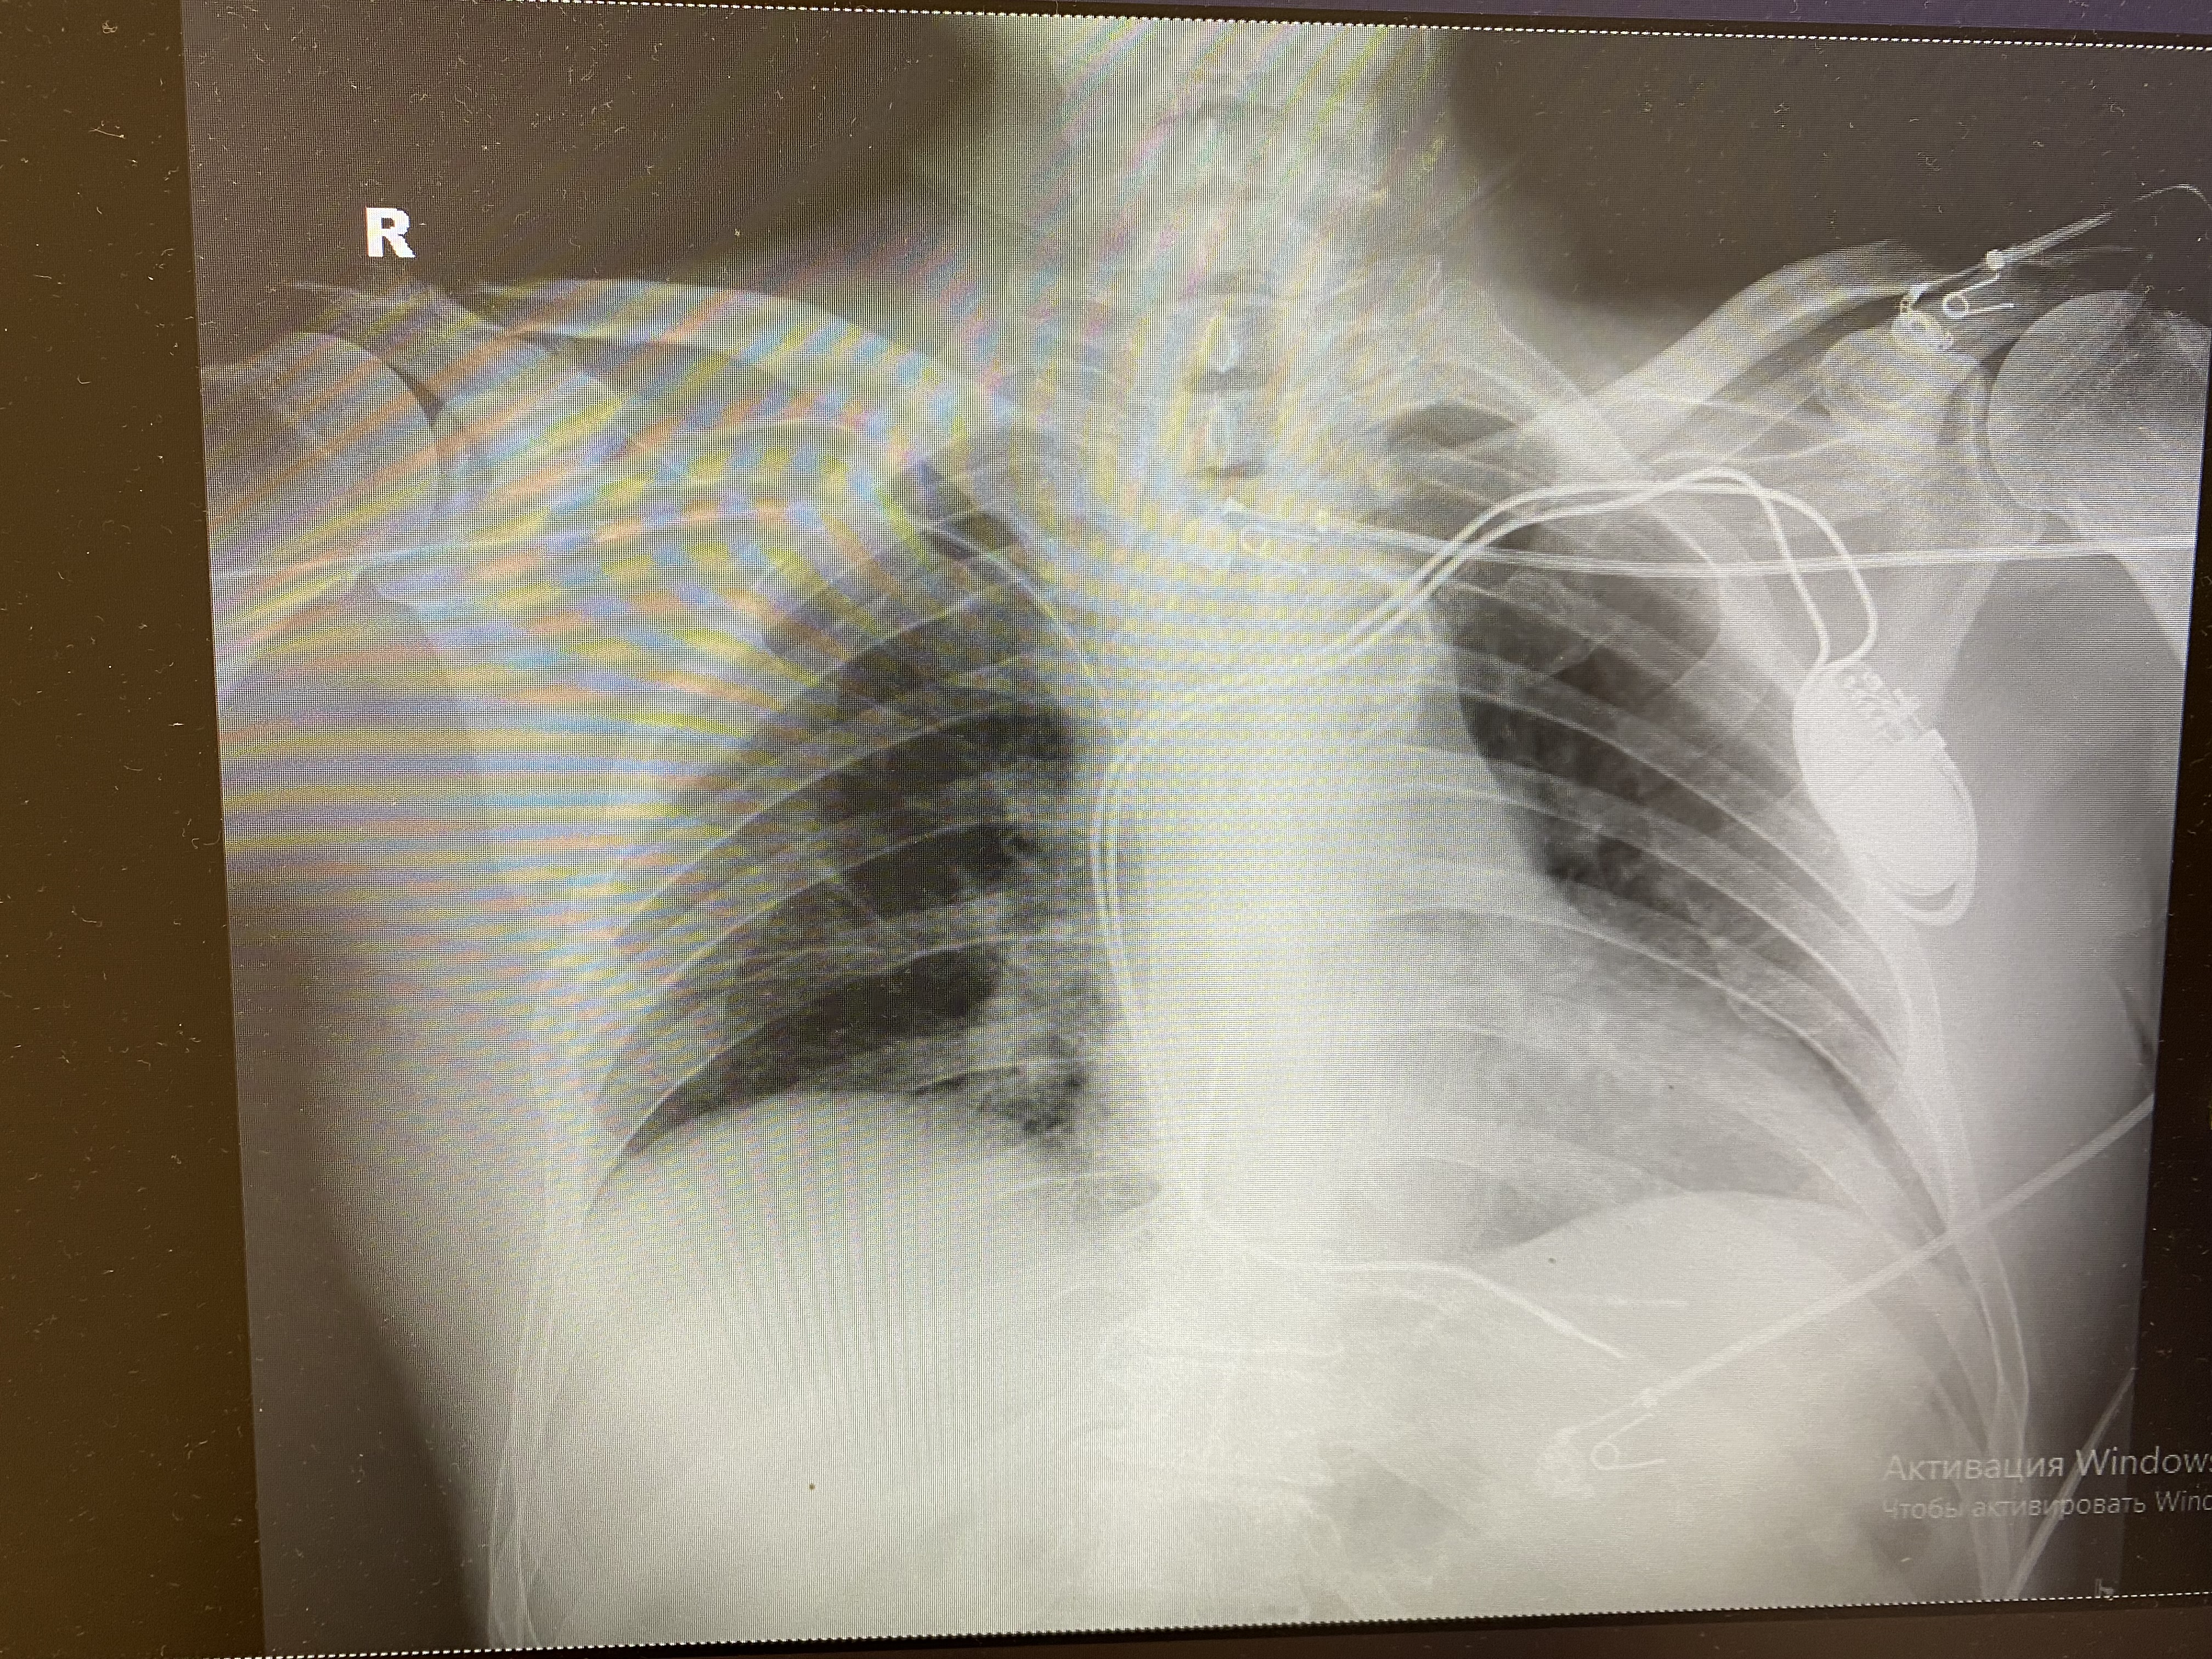

Работа времянки и постоянный вдруг ожил

IMG_0840.jpg

IMG_0840.jpg [ 1.73 MiB | Просмотров: 7796 ]

IMG_0846.jpg

IMG_0846.jpg [ 5.55 MiB | Просмотров: 7796 ]